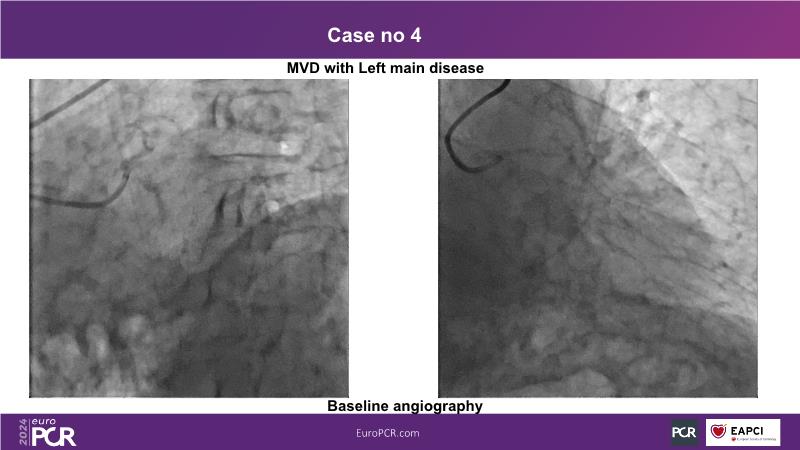

In this session, discover the effectiveness and safety of robotic PCI for both simple and complex lesions requiring additional devices like IVL, IVUS, laser, and FFR. Learn about the numerous benefits of robotics for patients and cathlab teams, including enhanced precision in wire navigation and stent positioning, full radioprotection, and reduced orthopedic injuries. Explore the growing interest in robotics within the interventional cardiology community, anticipate future technical advancements, and understand how AI will accelerate the integration of robotics and vice versa.

- To learn about a robotic PCI step-by-step from real-life experience